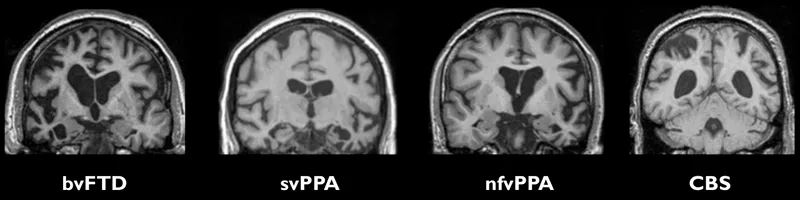

- Neuroimaging: Crucial for diagnosis.

- MRI: Shows characteristic, often asymmetric, atrophy in the frontal and/or temporal lobes.

- Neuroimaging reveals focal atrophy of the frontal and/or temporal lobes.